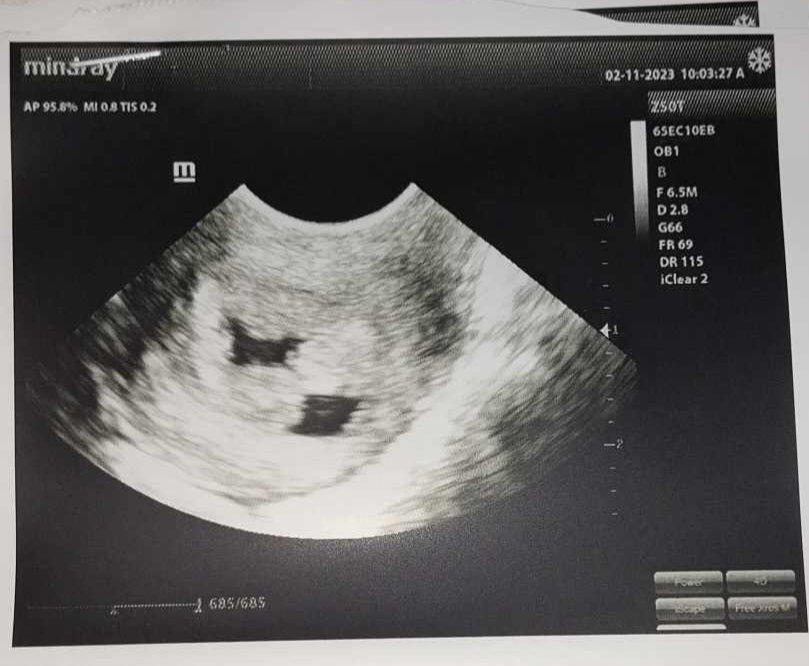

قراءة اشعة سونار علي الرحم